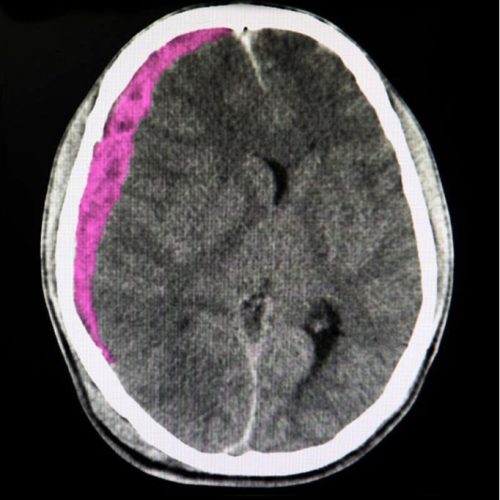

Εμφάνιση αιματώματος μέσα στο εγκεφαλικό παρέγχυμα - Ενδοκοιλιακή αιμορραγία

Εμφάνιση αιματώματος μέσα στις κοιλίες του εγκεφάλου. Εξαιτίας της ενδοκοιλιακής αιμορραγίας μπορεί να αναπτυχθεί αποφρακτική υδροκεφαλία, η οποία πολλές φορές είναι απειλητική για τη ζωή των ασθενών.